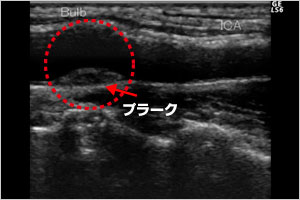

※実際は、このような超音波画像が見られます。

図3は、プラーク(矢印)のできた頸動脈の画像です。血管壁が隆起して白く写っている部位がプラークです。